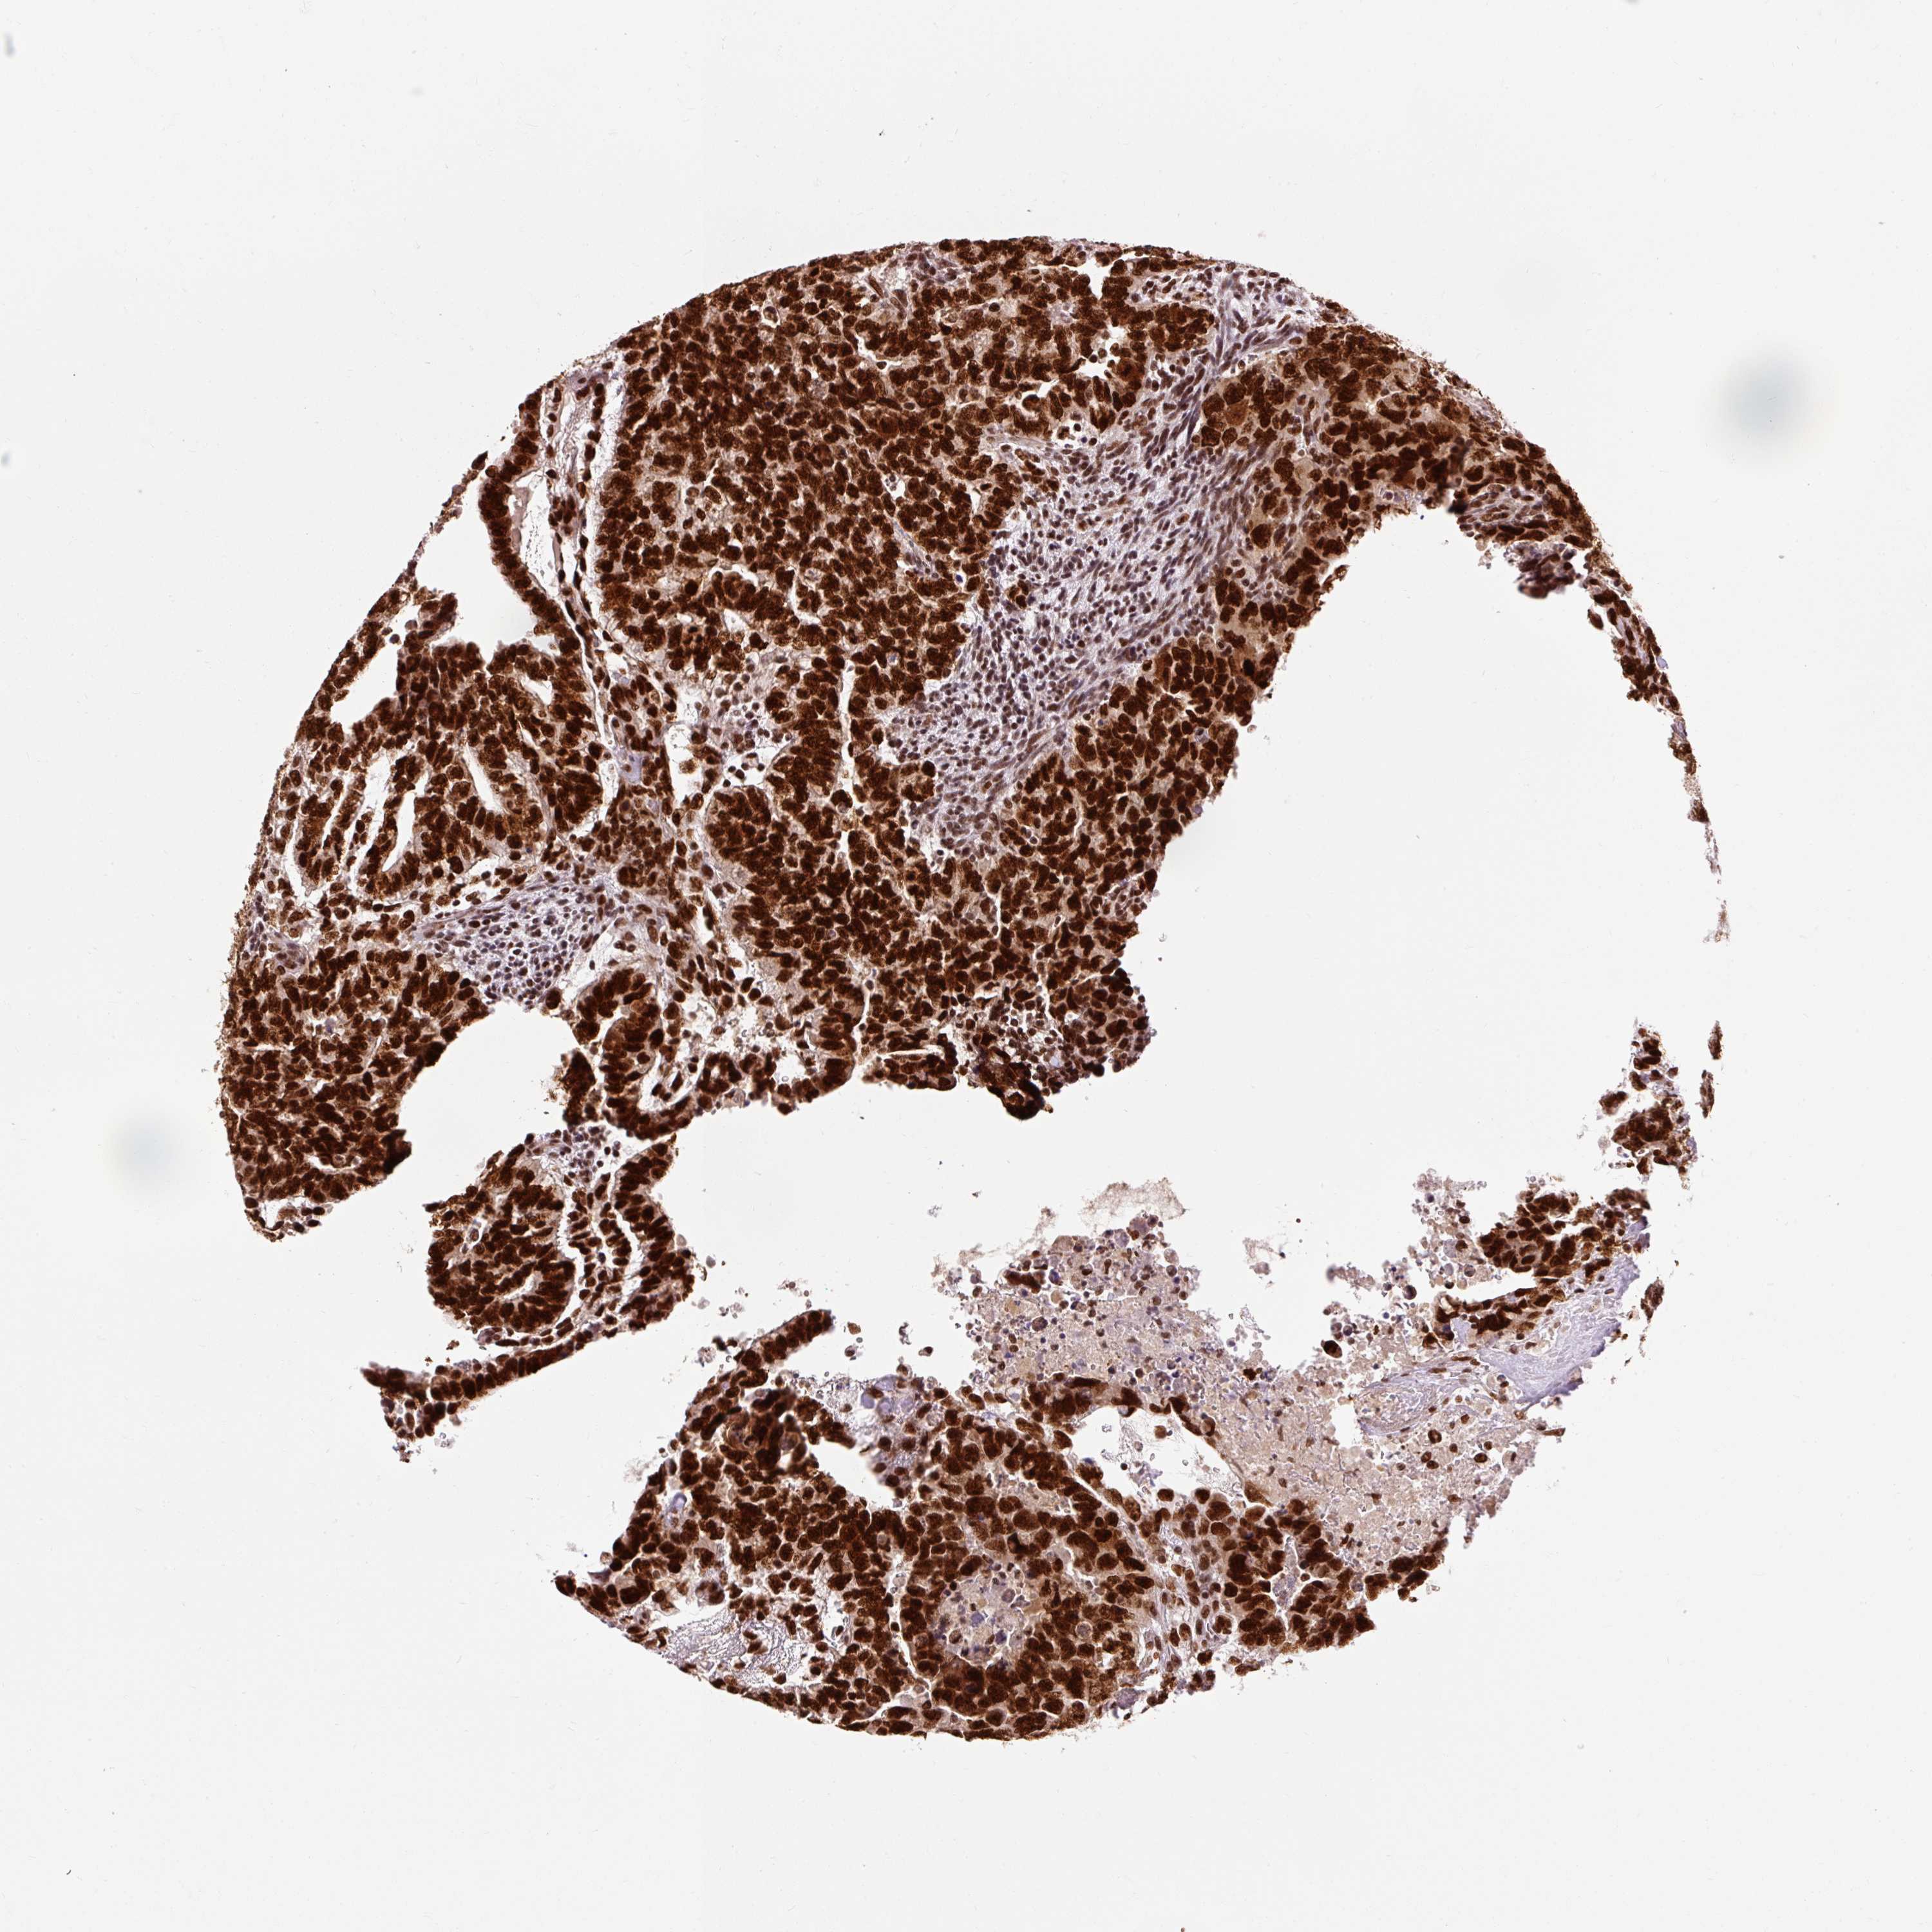

TESTIS CANCER - Protein expressioni

A mouse-over function shows sample information and annotation data. Click on an image to view it in a full screen mode. Samples can be filtered based on level of antibody staining by selecting one or several of the following categories: high, medium, low and not detected. The assay and annotation is described here.

Note that samples used for immunohistochemistry by the Human Protein Atlas do not correspond to samples in the TCGA dataset.

Antibody stainingi

Antibody staining in the annotated cell types in the current human tissue is reported as not detected, low, medium, or high, based on conventional immunohistochemistry profiling in selected tissues. This score is based on the combination of the staining intensity and fraction of stained cells.

Each image is clickable and will lead to virtual microscopy that enables deeper exploration of all samples and also displays staining intensity scores, fraction scores and subcellular localization as well as patient and tissue information for each sample.

Antibody HPA052589

Carcinoma, Embryonal, NOS

Seminoma, NOS